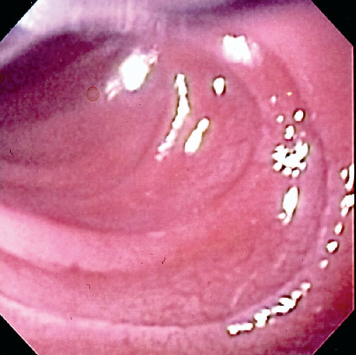

Abdelkader Hawasli, MD; Laura Stewart, MD; Hernando Lyons, MD

A 4-year-old boy presented with a 3-week history of intermittent nonbloody diarrhea, nonradiating periumbilical abdominal pain that was relieved by passing stool, and a 1.8-kg weight loss. No vomiting,...